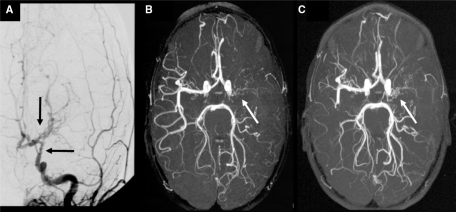

What's the Diagnosis?